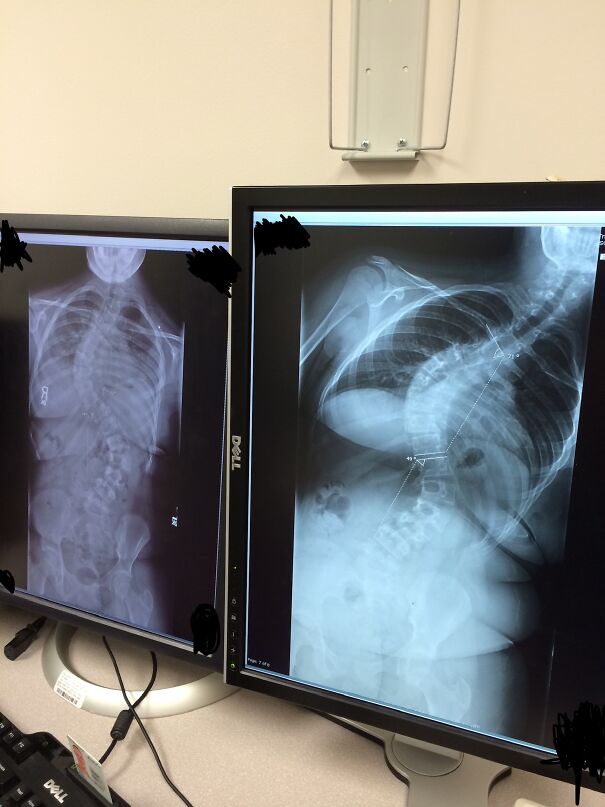

I had to get a chest X-ray as a teen in order to rule out possible pneumonia (turns out I just had bronchitis). This is not the mistake. Fast forward a year later, and I was diagnosed with severe scoliosis. I had both a top and bottom curve, with surgery as the only treatment option. My mom was kind of kicking herself for never noticing, but then she remembered I had gotten that X-ray. Her and my dad went back and forth for a while about if the X-ray might have shown anything (she said it did, while he didn’t think so), and it eventually got to the point where my mom went to the hospital and requested a copy of it. Not only did it show the top curve, but the technician actually had made a point about it in the notes, and for me to be informed in order to follow up with my regular doctor immediately. The ER doctor never mentioned anything beyond "no pneumonia". So basically, I could have gotten my scoliosis diagnosed an entire YEAR earlier! Or at least been made aware of the fact that I had it.